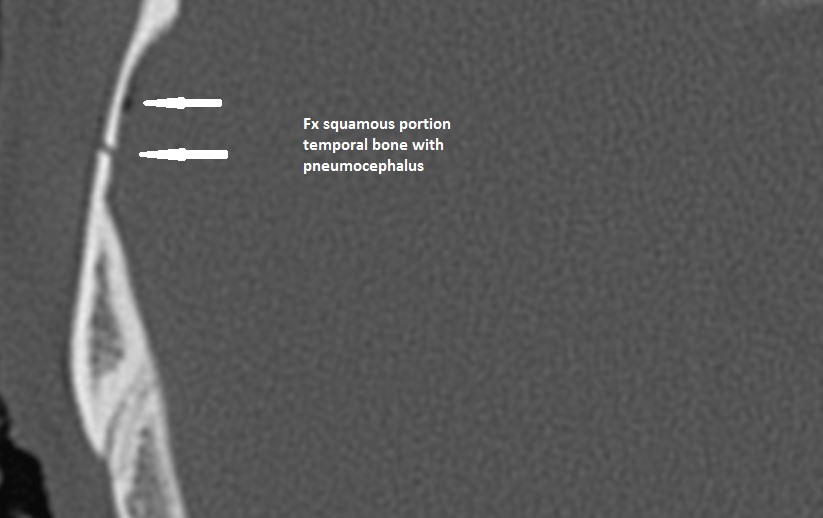

There is a calvarial fracture.

There is subperiosteal, epidural or subdural hematoma and/or pneumocephalus along the boney walls of the anterior, middle or posterior cranial fossa or elsewhere.